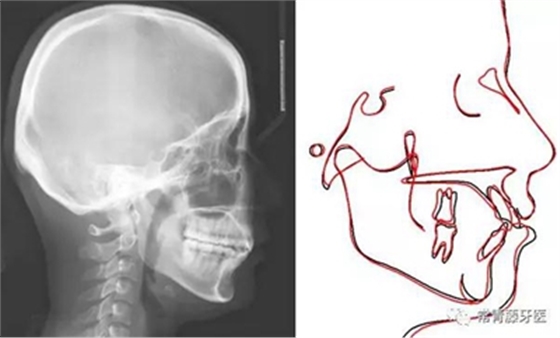

影像學(xué)檢查

頭影測(cè)量顯示上下頜骨發(fā)育不足,且呈現(xiàn)骨性Ⅱ類。

術(shù)前術(shù)后描記圖顯示上牙列整體遠(yuǎn)移有效,表現(xiàn)為磨牙遠(yuǎn)移及上前牙內(nèi)收(黑色術(shù)前,紅色術(shù)后)。